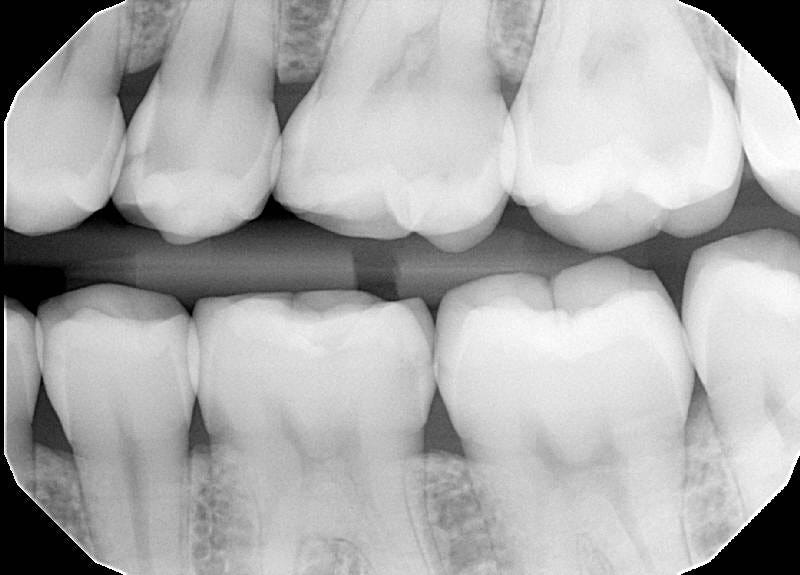

He angled my head, mouth agape, toward a handheld mirror. Be-gloved and masked-up with tools deep in teeth he gestures towards a visible cavity in the upper right conclave of my gob. “See there?” he says. I do see there. It’s a surprise - a small, painless, and mucky-coloured shade of decay reaching surreptitiously out of a molar. I try to respond as is expected; “oh no!” I exclaim. It comes out muffled and tastes metallic. With tongue unable to hit palate it escapes as a tangled moan. “Ouwgh nauogh!”.

“Be careful what you drink, dear”, he says as we close our appointment, him blithely adjusting the contrast on an x-ray of my teeth, me being mechanically reanimated by a dental chair rising slowly on its hinge. “Have a think on the white caps”.